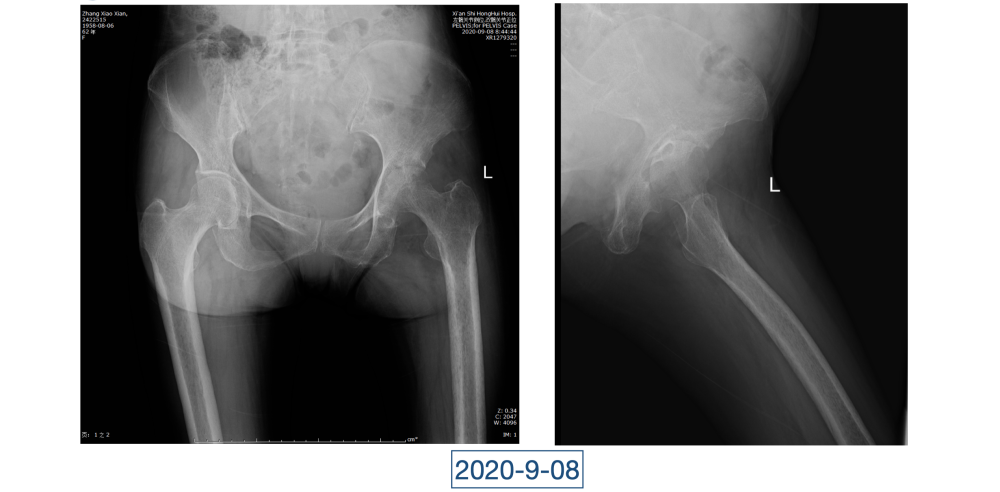

一直到了四月,因为髋关节疼痛的原因,她又来到红会医院关节病医院。李辉见到的黄大娘是坐着轮椅的,家里人说她已经到了卧床不起的地步,原本近107斤的人只用了3个月时间就瘦到了34斤。“这是患上了什么大病,才能让人变成这个样子?”看着憔悴不堪,可以用皮包骨头来形容的黄大娘,李辉心里一沉,担心起来。

全身上下11处骨关节被破坏!密密麻麻的诊断看得李辉毫无思绪,这么久都查不出来的病因能让他查出来吗?一时间,他也说不出话。看着黄大娘深深凹陷的双眼,浑身上下几乎看不见肉,就像罩着一层饥饿的青黄色的薄皮。过了好一会儿,他叹了口气,说:“先住下吧,用药把关节疼痛缓解一下,再想办法。”